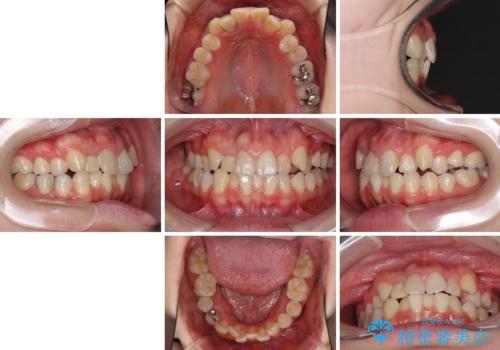

狭い上顎骨を拡大 インビザラインによる非抜歯矯正

- 上下のデコボコと奥歯の咬みにくさを気にして来院された患者様です。

上顎骨の幅が下顎骨よりも小さいので、拡大装置により骨幅を広げて上下関係を改善し、その後インビザラインにて歯並びを整えることとしました。